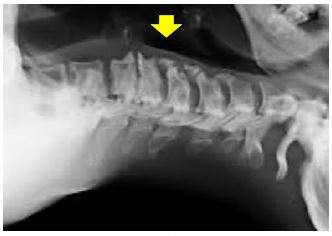

- Prominent osteophytes may impair advancement of the scope and make traumatising the mucosa more likely (Figure 28)